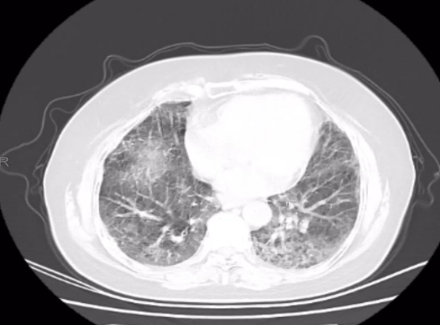

CT 影像:11 月 27 日复查胸部 CT,可见双肺磨玻璃渗出影明显吸收,对比 11 月 18 日影像,肺部病变改善显著。

11月18日肺部 CT

11月27日肺部CT